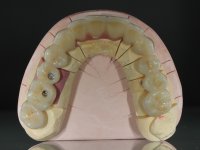

Foram realizadas impressões em alginato a ambas as arcadas, acompanhadas pelo registo das relações inter-maxilares e recolha de informação com arco facial. No laboratório foi confecionada uma ponte provisória de 13 elementos em acrílico autopolimerizável na qual foi incorporado um reforço metálico. Os dentes 1.7/1.4/1.3/2.2/2.3/2.4 e 2.6 foram utilizados como pilares. A ponte metalo-cerâmica foi removida após a realização de cortes longitudinais feitos com brocas diamantadas. Os preparos dentários foram re-preparados e a ponte provisória foi rebasada em boca com acrílico auto-polimerizável. Após a confeção da ponte provisória, foi confecionada uma epítese gengival em resina composta com tonalidade gengival, com o objetivo de funcionar como uma maquete, que permitisse à paciente pré visualizar a possibilidade de utilização de cerâmica de tonalidade gengival no trabalho final. Esta opção foi aprovada como válida pela paciente. Posteriormente foi planeada e executada a colocação de dois implantes no primeiro quadrante. O monobloco provisório foi retirado para a colocação dos implantes e após a cirurgia foi novamente cimentado provisoriamente. Passado o período de osteointegração foram realizadas as impressões ao maxilar superior. Na zona anterior foram utilizados fios de afastamento gengival impregnados e nas zonas posteriores foi utilizada pasta de caolino. A impressão aos implantes utilizou a técnica de moldeira aberta. O material de impressão utilizado foi o silicone de adição putty soft e regular, ambos de presa rápida. No laboratório, o modelo das restaurações provisórias e a maquete em resina serviram de orientação ao enceramento da infra-estrutura. O modelo de trabalho em gesso e o enceramento da infraestrutura foram colocados num scanner laboratorial e deram origem a um modelo de trabalho digital no qual foi sobreposta a digitalização da infraestrutura encerada. Esta sobreposição facilitou o desenho CAD da infraestrutura em Zr. Posteriormente, o desenho CAD por um processo CAM de fresagem deu origem às peças de Zr. A infraestrutura foi pigmentada com uma coloração rosada, que favorecesse a colocação posterior de cerâmica de tonalidade gengival. Durante a modelação da infraestrutura foi detetada a necessidade de aumentar o desgaste oclusal no dente 1.4. Este desgaste foi feito no modelo de trabalho real e foi confecionada uma guia de controlo de desgaste em acrílico que acompanhou a prova das infraestruturas. Em boca foi realizado o desgaste corretivo e foi realizada a prova das peças de Zr. Durante a prova foi reavaliada a escolha da cor da cerâmica de tonalidade gengival. O tratamento foi finalizado no laboratório e após aprovação pela paciente foi colocado definitivamente em boca.